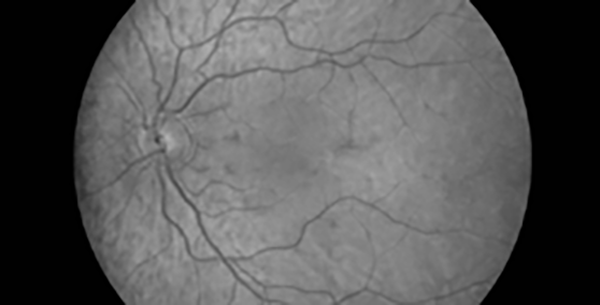

Nel VX620 il separatore di lunghezze d’onda permette di visualizzare in un’unica schermata: nella parte superiore l’immagine originale, quella infrarossa e quella rosso-priva; nella parte inferiore quella coroidale, vascolare e le fibre

nervose.

Gli strumenti di misura integrati nel software VX consentono di calcolare facilmente il rapporto C/D (cup-to-disc) per il rilevamento delle patologie legate al Glaucoma.

VX620 consente l’acquisizione di più immagini, al fine di ricreare una visione panoramica delle aree retiniche più periferiche.